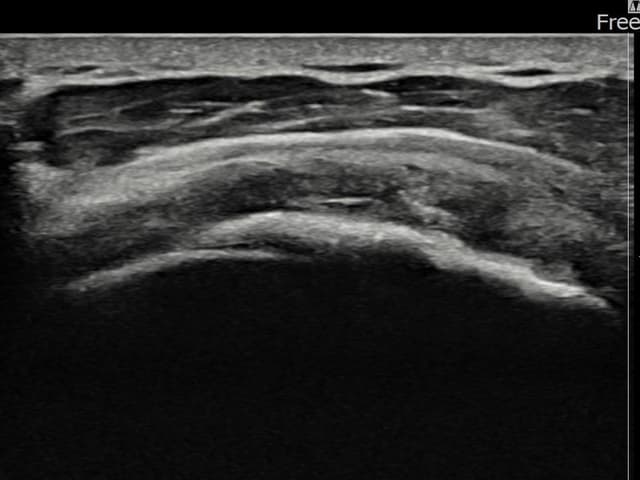

左侧 冈上肌腱 石灰化肌腱炎

9mm × 7mm